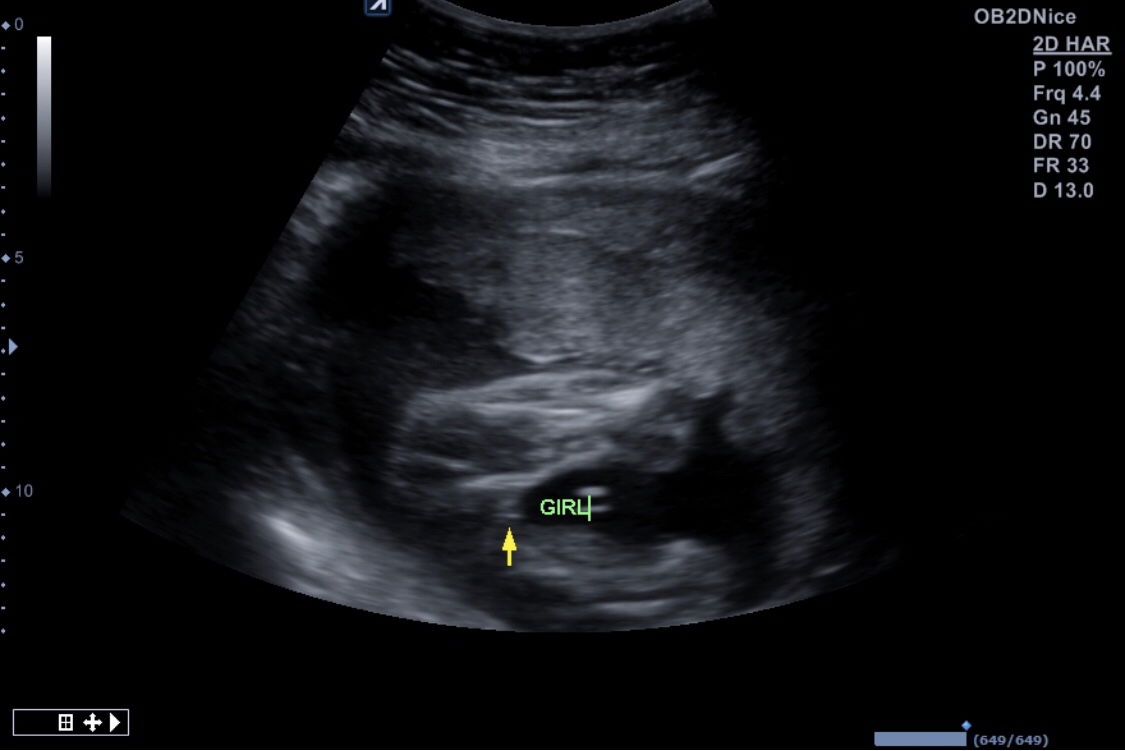

Detail scan baby gender girl. Korang rasa girl ke boy?

Okay so I buat detail scan saying it’s a girl. Tapi maybe sometime mommy had a boy when the whole time the doctors cakap it was a girl. I’m just so scared that it’s wrong sebab I already have a whole lot of baby girl clothes! What does it look like to you guys??

Baby tu x kepit kaki dan npk jelas 'burger' nya.. So it's a girl..